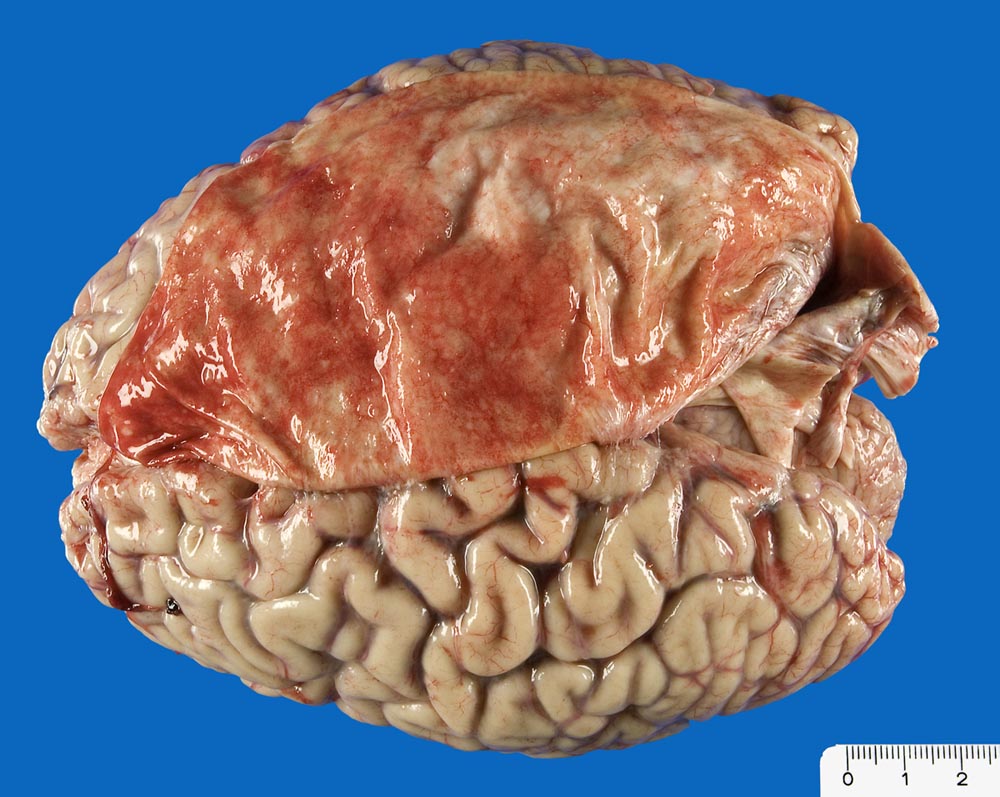

Makroskopisch bilden invasiv duktale Karzinome knotige weissgelbe Tumoren von harter Konsistenz mit sternförmigen Ausläufern. Das Fettgewebe in der Tumorperipherie ist meist auf einer Breite von 1-3mm orange verfärbt. Mammakarzinome können multifokal (mehrere Herde innerhalb eines Quadranten mit Abstand von weniger als 4cm) oder multizentrisch (> 2898) (Tumorherde in verschiedenen Quadranten mit mehr als 4cm Abstand) wachsen.

Makroskopie

Befund

Pathologischer Befund